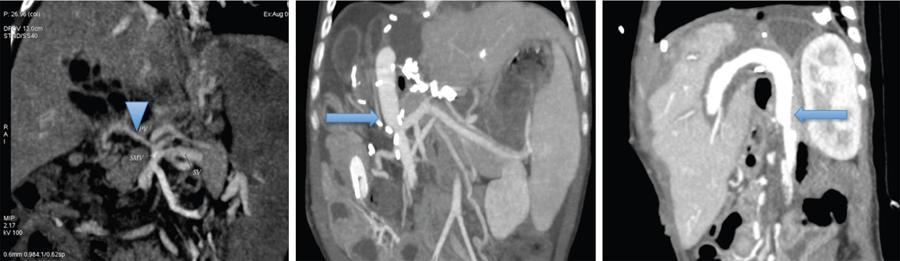

It is also important to note the diameter of the portal vein as size discrepancy between the donor and recipient PV may also necessitate a venous graft to connect the SMV to the PV (Fig. 9.14.4). Flow pattern in the portal vein also needs to be assessed and in cases of centrifugal and reduced flow in the PV, ligation of any major shunt or collateral can be considered to achieve optimal PV flow for the transplant liver to avoid posttransplant PV thrombosis.

Preoperative identification of portosystemic shunts and varices

This is also very important, as these may be ligated at surgery to optimize blood flow towards the graft liver. Closure of large shunts can be planned preoperatively with percutaneous intervention (Fig. 9.14.5) if there is attenuation of portal vein calibre and reversal of flow seen in the portal vein in preoperative Doppler imaging. Preoperative identification of these may also minimize dissection time and risk of haemorrhage.

During TIPS placement, the superior tip of the shunt is normally in the right hepatic vein (RHV) or inferior vena cava (IVC) and the inferior tip is in the right portal vein or main portal vein (Fig. 9.14.6C). Shunt-related vessel lumen stenosis and migration of the shunt are important complications in patients with TIPS that can affect transplantation by increasing the time spent on bypass and complexity of transplant operation.

In cases of low inferior shunt tips or inferior stent migration, the shunt extends into the extrahepatic part of the main portal vein, this portion of the portal vein may also need resection due to scarring of the endothelium. This results in a decreased length of portal vein available for anastomosis to the donor liver. The relationship and distance of the stent tip in the main portal vein to the splenomesenteric confluence can be documented and better shown on three-dimensional (3D) images.